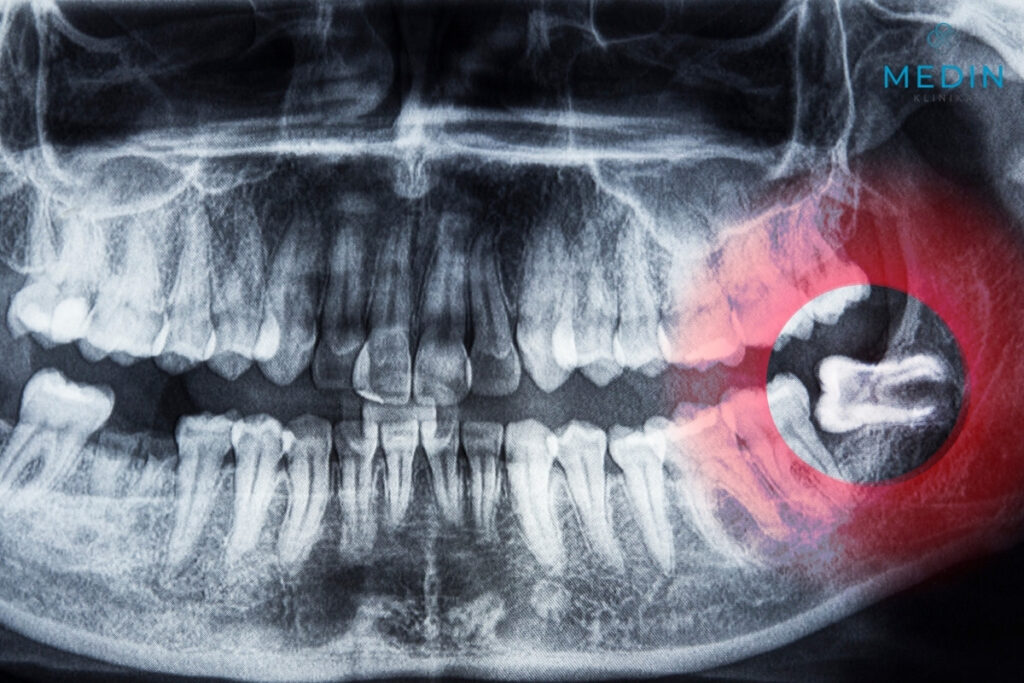

- Zatrzymane ósemki – częściowo lub całkowicie ukryte w kości, niemożliwe do prawidłowego wyrznięcia.

- Nieprawidłowe ustawienie – zęby rosnące pod kątem, które naciskają na sąsiednie trzonowce, prowadząc do ich przesuwania i bólu.

diagnostyka radiologiczna (zdjęcie panoramiczne, czasem tomografia CBCT) - Wywiad medyczny